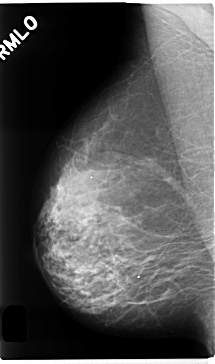

C_0259_1.RIGHT_MLO

RIGHT_CC LINES 4760 PIXELS_PER_LINE 2744 BITS_PER_PIXEL 12 RESOLUTION 50 NON_OVERLAY

RIGHT_MLO LINES 4720 PIXELS_PER_LINE 2784 BITS_PER_PIXEL 12 RESOLUTION 50 NON_OVERLAY